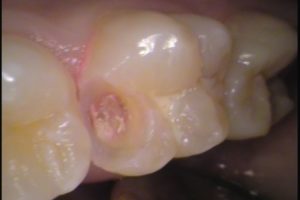

穴をあけてみると

黒い虫歯がでてきました・・・

もう少し掘り進めると、結構黒いですね(^-^;

ちょっと虫歯が大きいです。